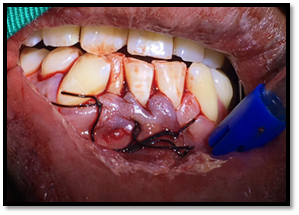

Cirugía propiamente dicha:

Se realizó la osteotomía para el retiro de los dentículos que está formando al odontoma, llegando a la extirpación de 13 dentículos.

Imagen 8. Odontosección.

Imagen 9. Remoción de Odontomas.

Imagen 10. Total de dentículos extraídos .

Se colocó FIBRINA RICA EN PLAQUETAS en la cavidad.

Vicril 0000, se suturó primero las papilas interdentales, luego la liberatríz. Siendo un numero de 4 puntos simple de sutura.

Imagen 12. Sutura.